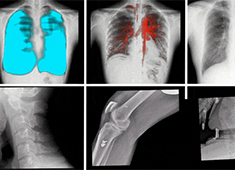

拍摄全脊柱X光片 长骨拼接技术和一板成像的区别

出于对全脊柱X光片的拍摄需求,DR长骨拼接和大平板一板成像这两项技术应运而生。长骨拼接技术是在DR自动控制程序模式下,通过多次连续曝光及图像采集(6至8次),将多幅有重叠部分的图像无缝拼接成一幅连贯的整体图像。...